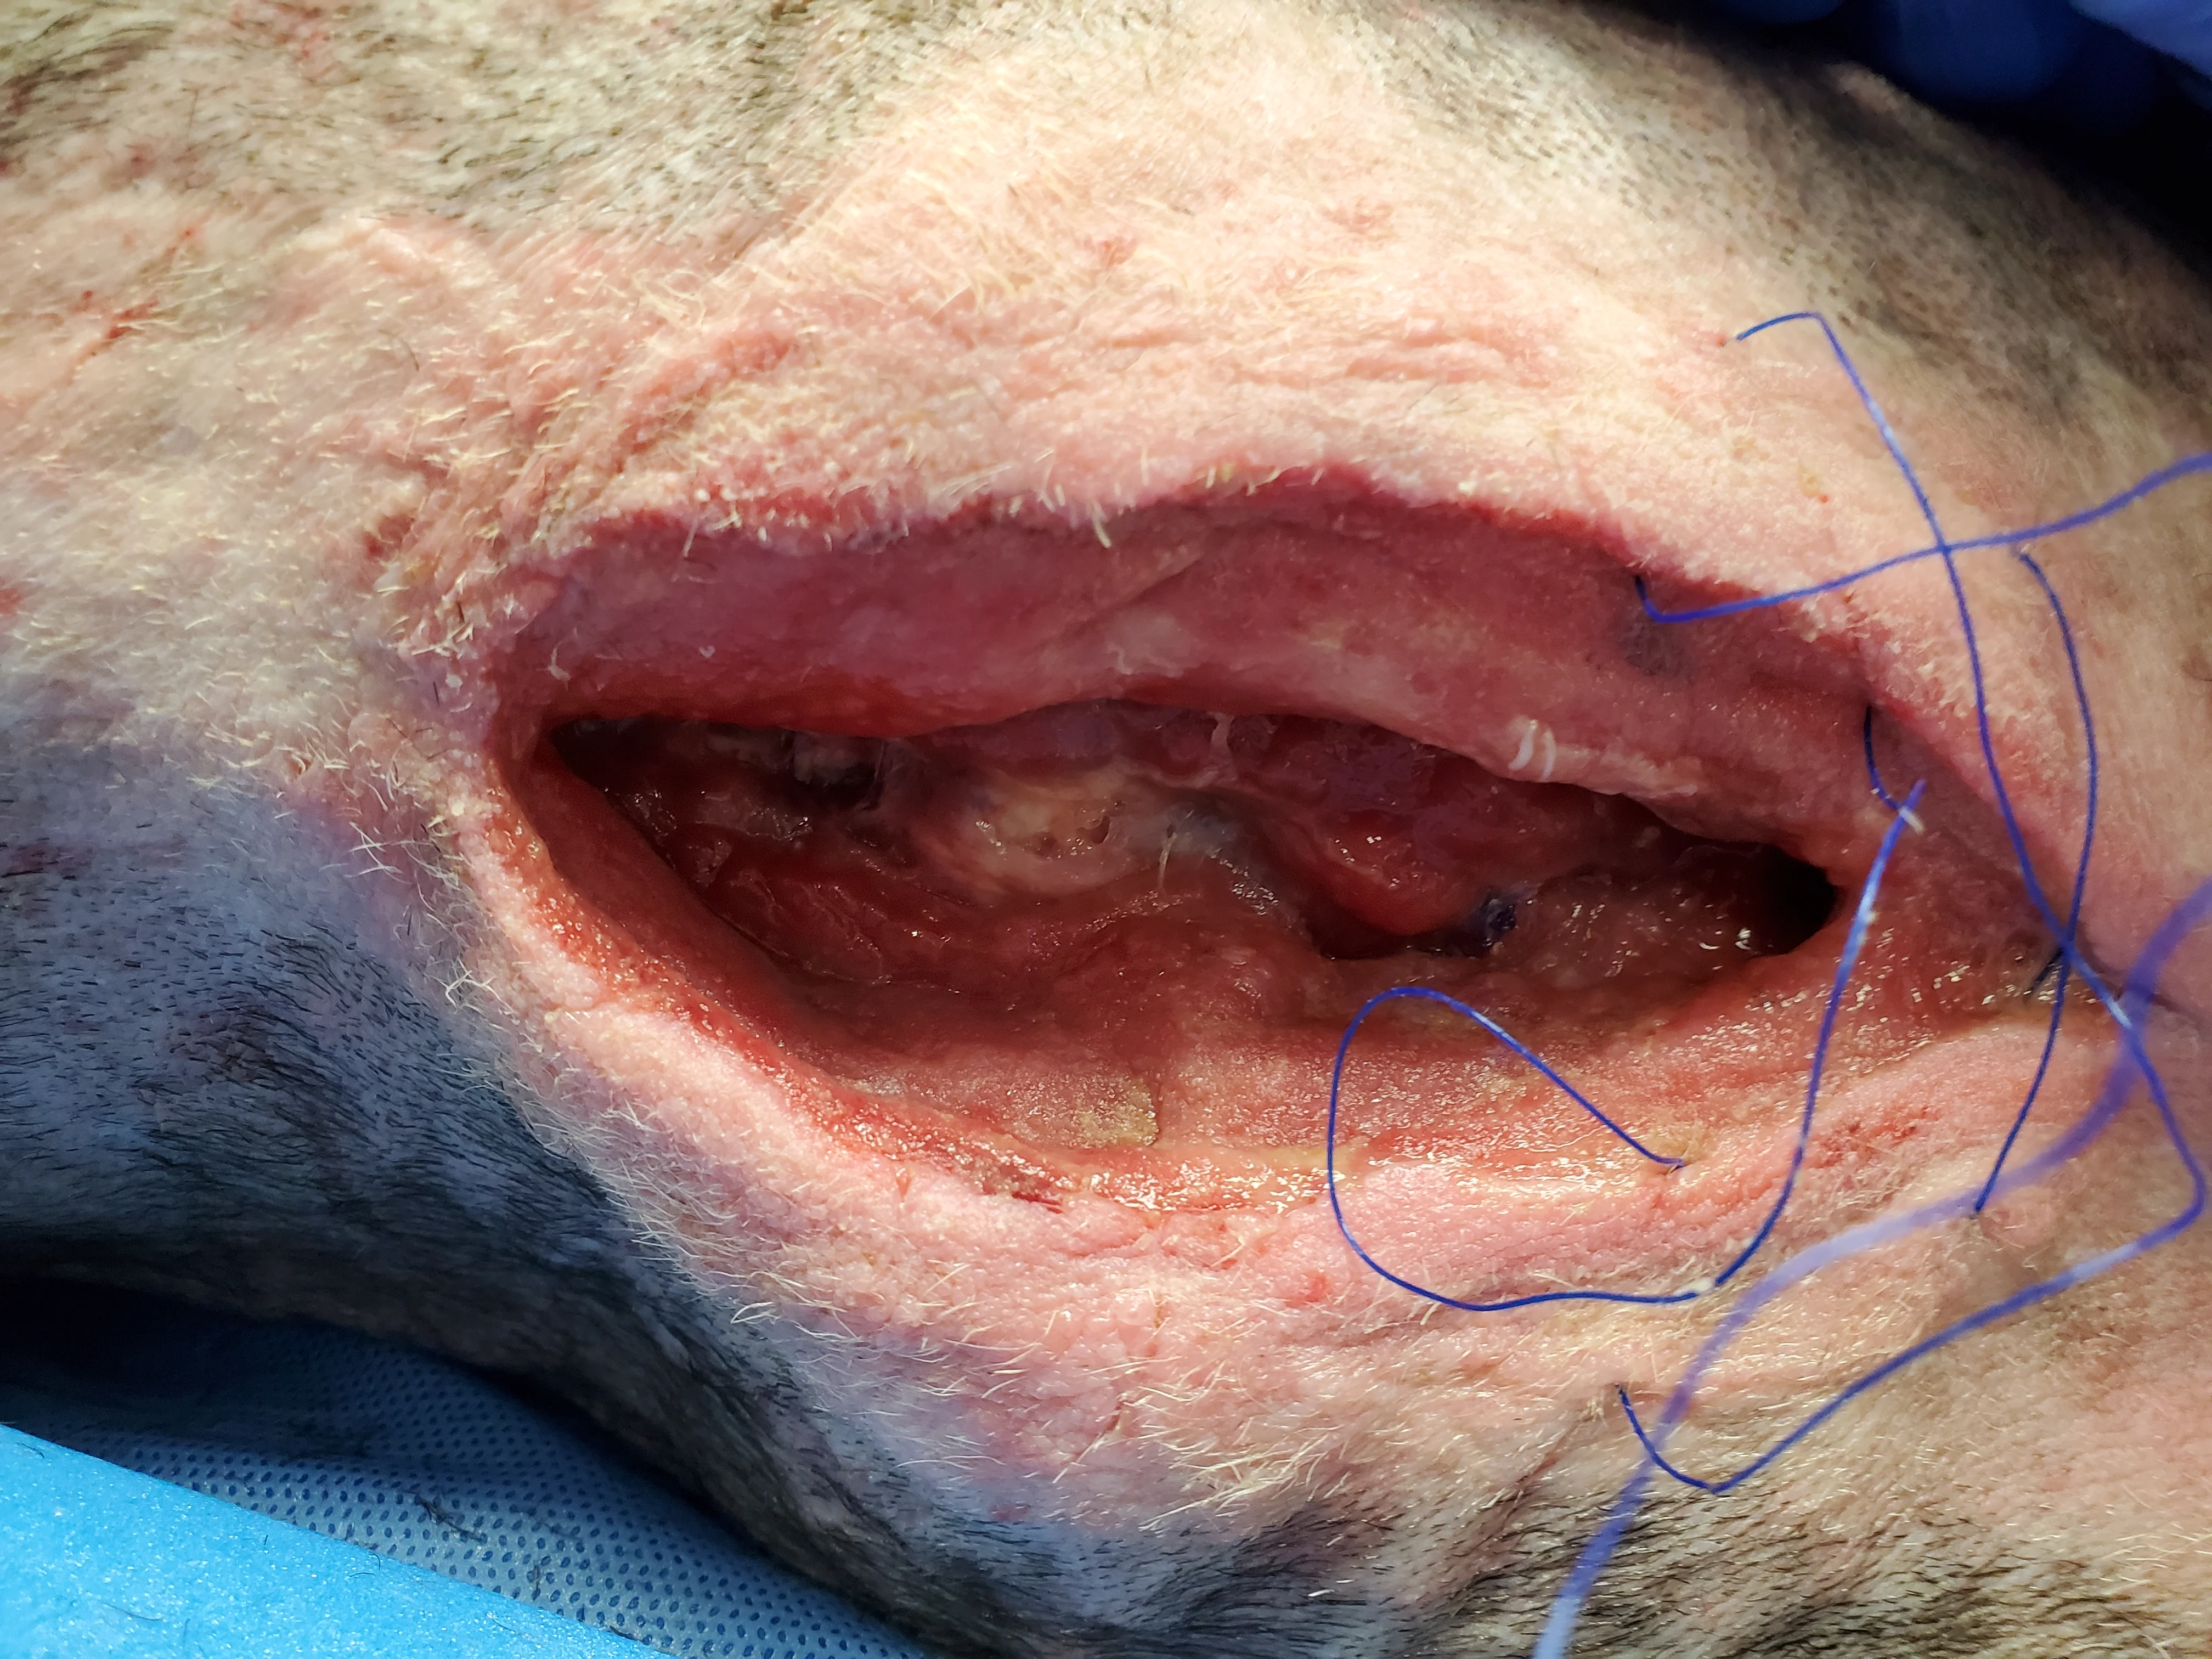

Figure 13 NPWT therapy should be continued until the wound is filled with granulation tissue. The wound can then undergo primary closure. Despite continued NPWT for 12 days, the wound in this patient became static, with minimal progression of granulation tissue development. A tissue culture taken after 9 days of NPWT was negative.

Failure of NPWT most commonly occurs if suction is lost.22 In addition, granulation tissue may not fill sites in which the foam sponge does not come into contact with subcutaneous tissues. Lack of response to NPWT is unusual but can occur with insufficient debridement.22 Other causes of delayed wound healing include persistent infection, biofilm formation, administration of immunosuppressive drugs, certain metabolic diseases (eg, uremia, hyperadrenocorticism, hypothyroidism), malnutrition, pressure, and radiation.25 In this dog, sternal osteomyelitis could have contributed to persistent infection, and additional radiographs may have been helpful in assessing the tissues.